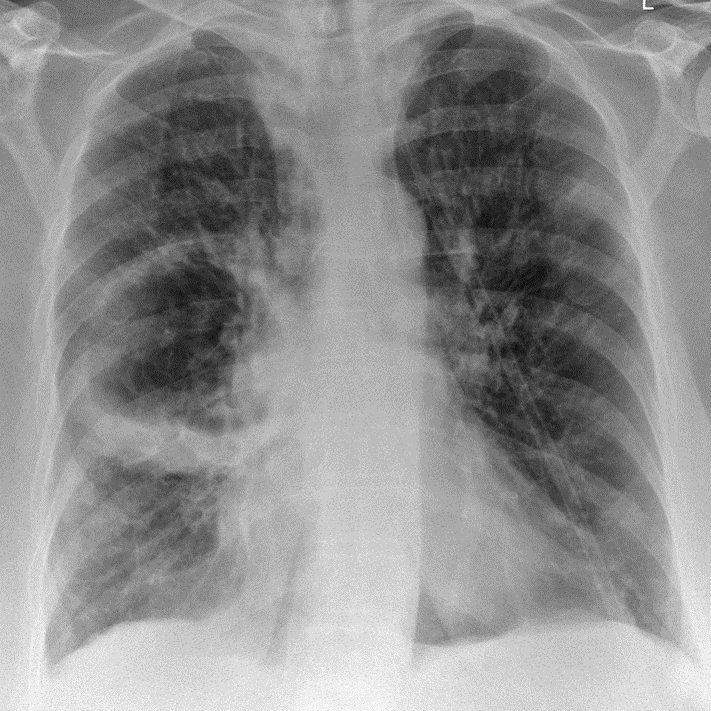

1-Ápxe phổi (P) thùy dưới